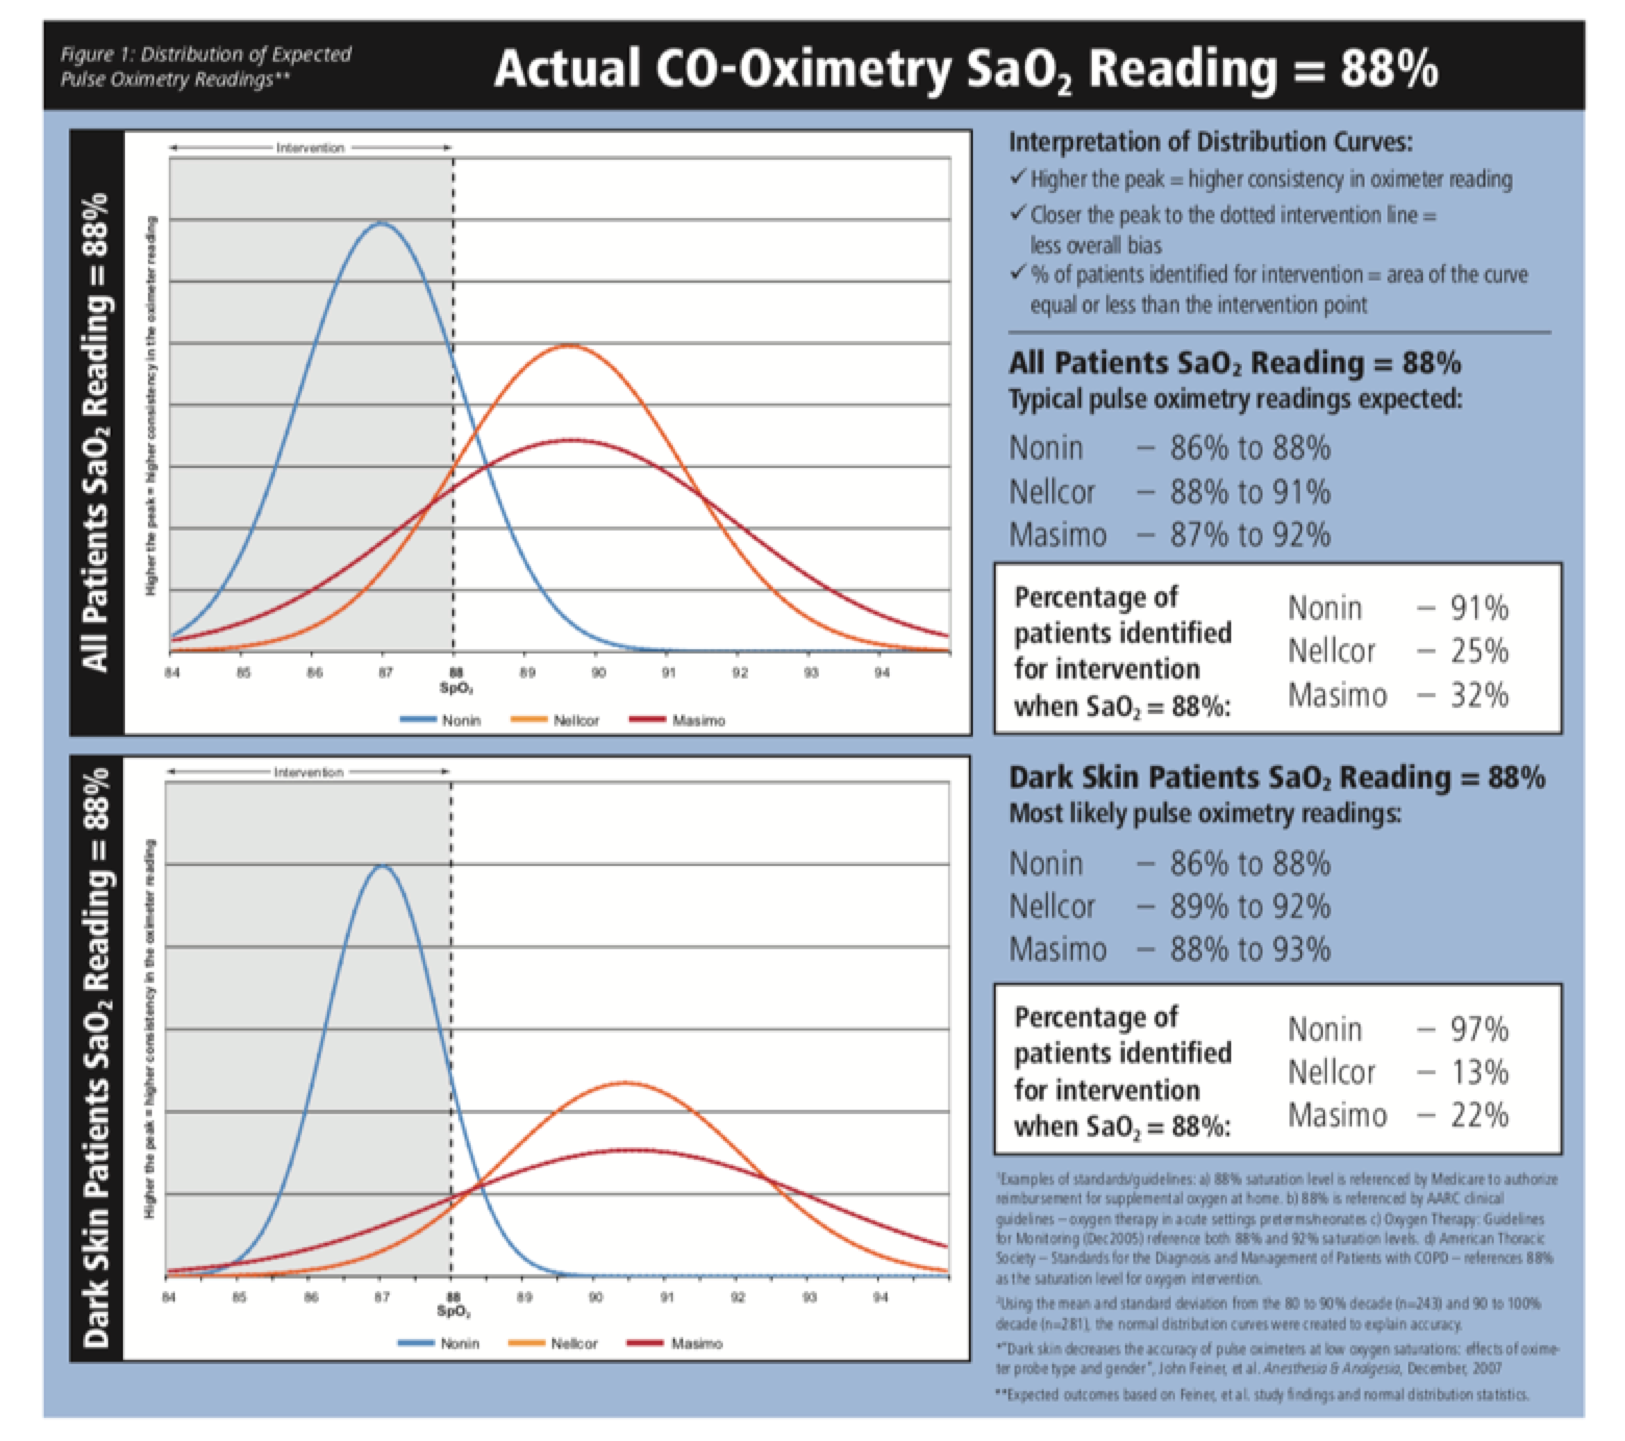

This might seem like a fine point, but medicine is made of fine points that turn into ordinary decisions. Using the UCSF data, one company’s illustrations demonstrate the skin color variability of three brands of pulse oximeters (Nonin, Nellcor, and Masimo) for one of the most common clinical decision points: a reading of 88 percent. Pulse ox readings can also be affected by conditions such as anemia, jaundice, poor circulation, and nail polish. Physicians in a clinic may not distinguish errors stemming from an underlying condition and those caused by the device’s bias on darker skin. The UCSF lab data are revealing on this point. The study participants were “healthy, nonsmoking” Black and white young people in their twenties and thirties, mostly UCSF medical students, none of whom “had lung disease, obesity, or cardiovascular problems.” This pool of participants allowed the researchers to isolate skin color calibration errors alone, eliminating misreadings due to underlying comorbidities.

Image courtesy of Nonin Medical, illustrating the findings of Feiner et al. (2007). Nonin Technical Bulletin, September 2008.

Most hospital protocols now recommend starting oxygen at 90. Below that threshold damage to vital organs such as the heart, brain, lungs, and kidneys becomes an immediate danger. In a mixed general population, a true blood oxygen saturation of 88 percent would, on average, produce a pulse ox reading of 89 to 90 using the most common meter in hospitals. In that case, guidelines would correctly suggest going on oxygen. But Black patients, equally in crisis at 88, would get an average reading of 91—just above the intervention threshold.